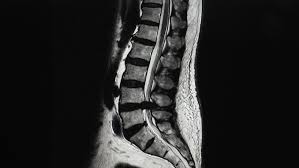

Because clinical signs alone may not be enough, an MRI scan is the most effective test. It shows the spinal cord and nerve roots clearly and helps identify the cause of compression.